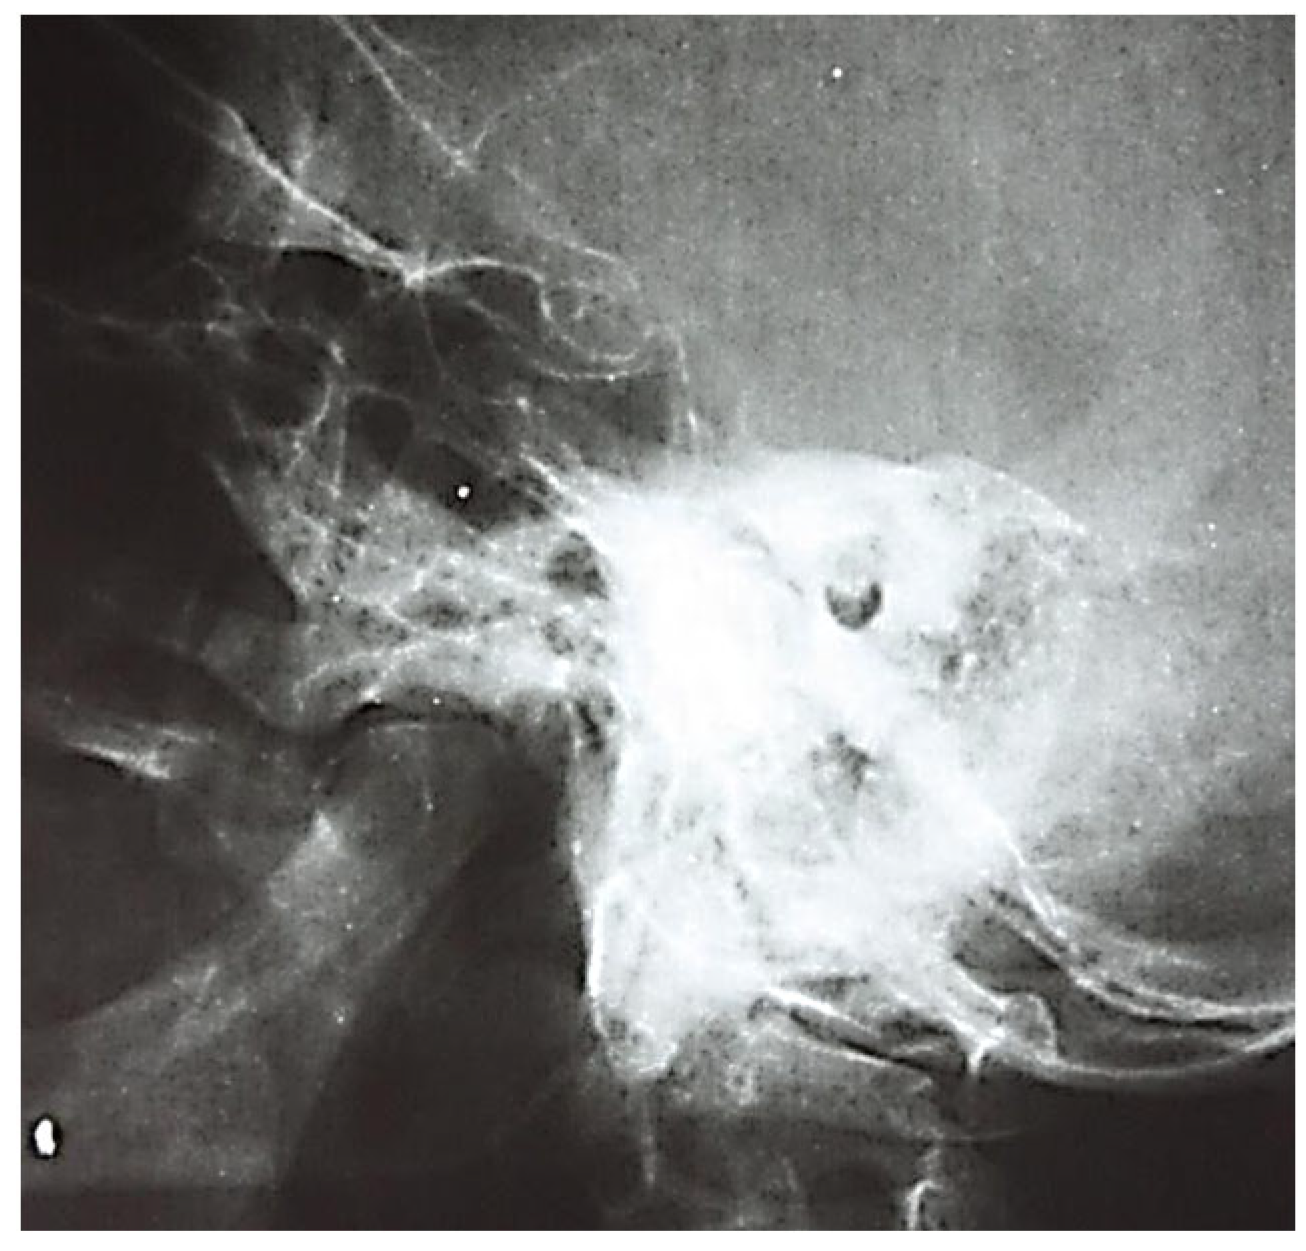

3.1.1. Conventional Radiology